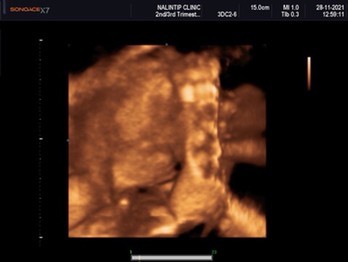

ซาวด์4มิติ ตอนนั้นอายุ25w1d ปัจจุบัน 27w4d ได้ลูกสาวค่ะดิ้นเก่งมากก😊